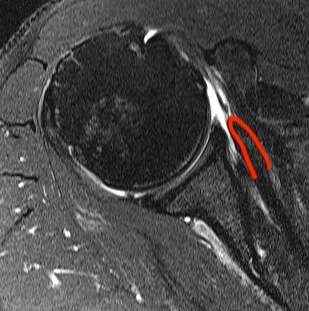

Perched long head of biceps with tear of upper border of subscapularis

Full thickness minimally retracted subscapularis tear